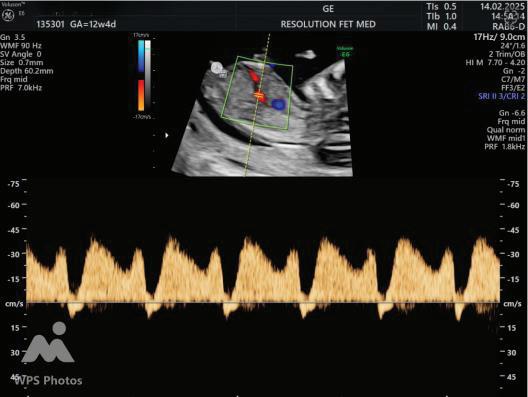

ADDITIONAL SONOGRAPHIC MARKERS:

A Wave Reversal

MARKER

Ductus Venosus flow

Tricuspid Regurgitation

Tricuspid Regurtitation

SIGNIFICANCE

Reversed a-wave in aneuploidy or cardiac dysfunction

Suggests cardiac abnormality or aneuploidy